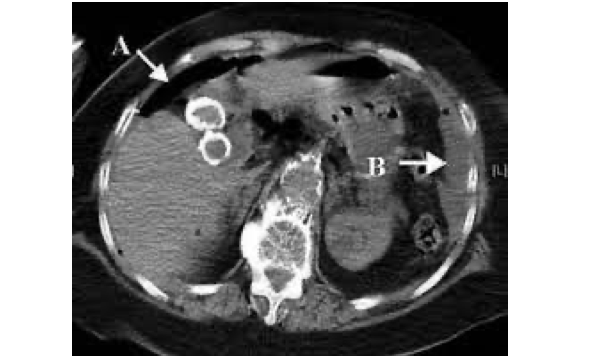

De flesta magsår som brister och perforerar är belägna i närheten av pylorus. Majoriteten av dessa är lokaliserade i duodenum. è Magsyra läcker ut i buken och retar peritoneum vilket resulterar i peritonit.